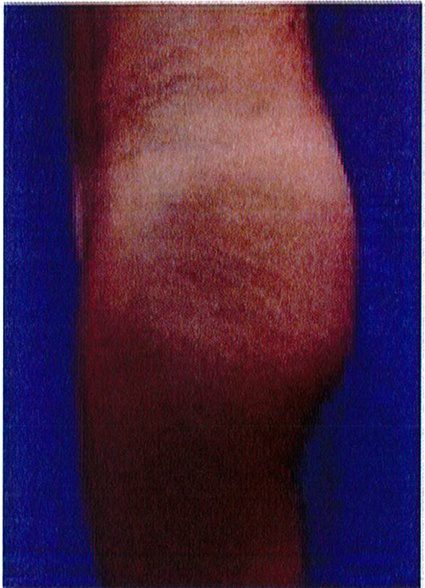

Hình. 18.. (A) Hình anh trước và (B) và sau phẫu thuật làm đầy mông của bệnh nhân được đặt khối implant dưới cân thể tích 225 mL, hai bên.

Bệnh nhân 31 tuổi tiền sử khỏe mạnh, có chỉ định nâng mông bằng implant do thiếu hụt thể tích. Hai khối anatomic implant 225 mL polyurethane dạng gel được đặt ở vị trí dưới cân. Sau phẫu thuật không ghi nhận biến chứng trong suốt quá trình hồi phục, vết mổ liền tốt (Hình 18).